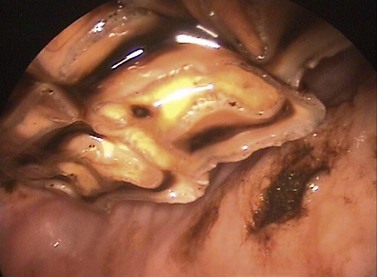

The endoscope is finally rotated to the buccal aspect of 106, and advanced caudally to identify diastema, displaced teeth and in particular, mucosal ulcers. The gag may need to be loosened slightly to enable sufficient cheek tooth retraction to thoroughly explore the buccal mucosa. Deep periodontal pockets are thoroughly cleaned using a pick and water jet and then re-examined for the presence of inflamed or granulating tissue (Fig. 12.17). The findings for each arcade are annotated into the dental chart, and the second arcade commencing with 206 is examined. The mandibular arcades are examined in a similar fashion. When examining the mandibular arcades, the lingual aspect of the arcade may be visualized more successfully if the tongue is retracted.

image

Fig. 12.17 Endoscopic view of a 310–311 diastema 3 months after periodontal treatment. Feed is no longer packing in the periodontal pocket, and the mucosa is healed. This photo was taken using a rigid endoscope with a 90° optic.